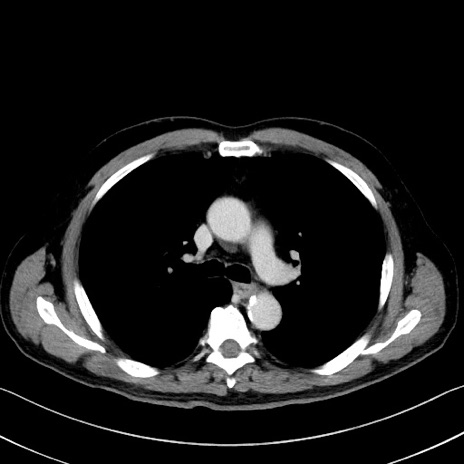

症例35(横断像)

【症例】70歳代 男性

【主訴】腹部膨満、嘔吐

【現病歴】昨日より腹部膨満感出現。本日増悪し、仙痛出現。嘔吐あり、受診。

【既往歴】糖尿病、胆摘後

【身体所見】BP 149/80mmHg、HR 74/min、BT 35.9℃、腹部:膨満、軟、圧痛なし。腸雑音減弱あり。上腹部正中切開瘢痕あり。

【データ】WBC 13500、CRP 1.72